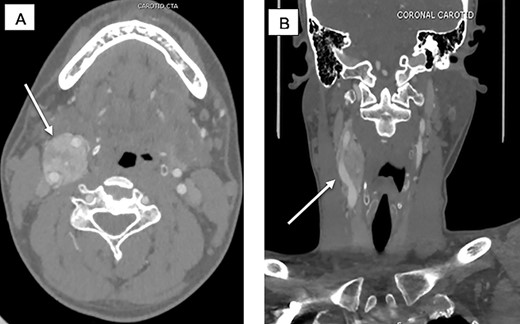

The CBT was nonfunctional and therefore no preoperative alpha blockade was needed. The patient underwent preoperative angiography and embolization by the interventional radiology team to decrease the risk of intraoperative bleeding given the size (7 cm) and the Shamblin III classification (Fig. 2A and B). The surgery was performed a week later by the surgical oncology team assisted by a vascular surgeon.

Preoperative embolization of CBTs remains a controversial topic. The risks include postembolization morbidity such as transient ischemic attack and even stroke by embolic particles [6].

The inflammatory effects of preoperative embolization could make precise subadventitial dissection more difficult. Benefits of preoperative embolization include decrease of tumor size facilitating complete resection and decreased blood loss. Currently, embolization seems to be beneficial for tumors larger than 5 cm, Shamblin’s type III, and those with significant cranial extension [7]. Correlation between preoperative embolization and vascular reconstruction has not been established.